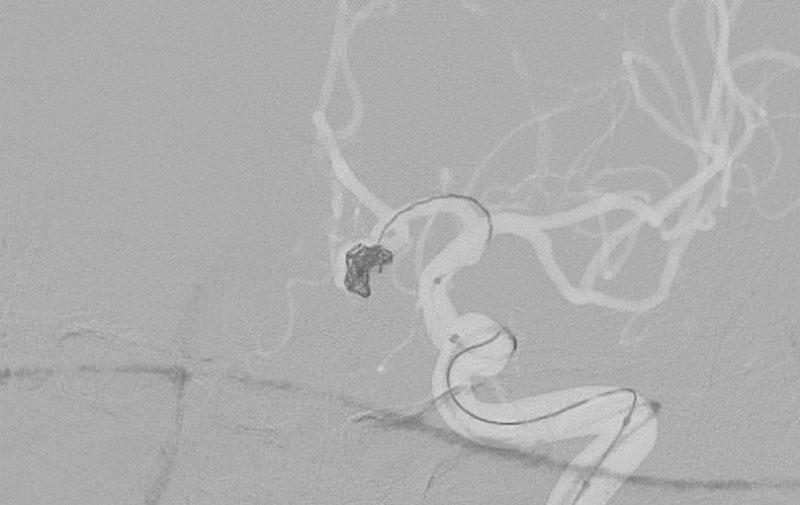

No.1591 手術中

硬膜動静脈瘻

50代

救急外来